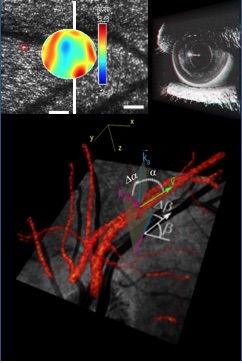

Functional imaging technologies are developed to analyze tissue function, in addition to obtaining the structural information of conventional OCT. These technologies comprise, among others, OCT angiography and Doppler OCT for qualitative and quantitative imaging of blood flow, spectroscopic OCT to measure parameters like tissue oxygenation, and optophysiology, a method that measures and quantifies tissue response to an optical stimulus by OCT signal analysis.

Contrast enhanced OCT imaging exploits other properties of light to provide additional image contrast: Polarization sensitive OCT can differentiate fibrous tissues by their birefringence and depolarizing tissues by their scrambling of the light’s polarization state. Multi-directional OCT exploits the anisotropic scattering properties of some tissues for contrast generation, and spectroscopic OCT uses the spectral dependence of the attenuation coefficient for tissue differentiation and for quantitative measurements.

For improved axial resolution, light sources with very large bandwidth can be used, e.g. Ti:Sapphire lasers and supercontinuum sources. With these sources, axial resolutions down to 1 µm and even lower can be achieved. For imaging of the retina, the lateral resolution is limited by the aberrations caused by the ocular media which only allows imaging with low NA. Adaptive optics OCT systems that correct for the ocular aberrations enable retinal imaging with cellular resolution.